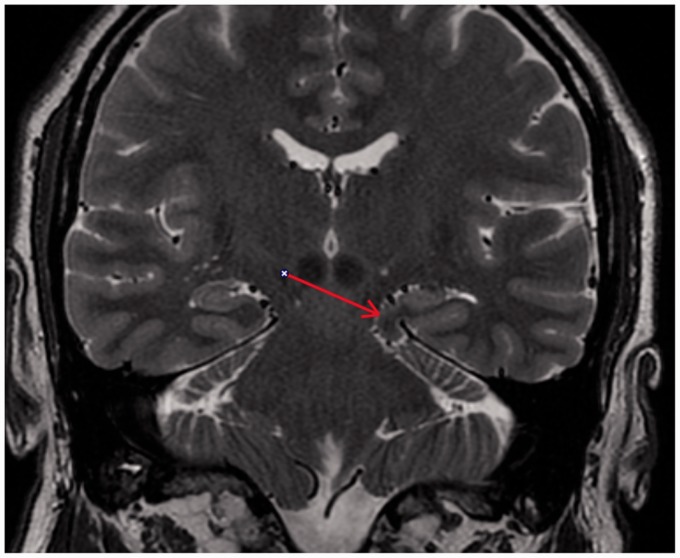

Idiopathic herniation of uncus and parahippocampal gyrus into the ambient cistern is a very rare entity, which could be mistaken for other pathology such as tumor. To the best of our knowledge, two prior cases of this kind of herniation have been described. One of these cases was with associated symptomatology and other abnormalities, and the other was characterized as idiopathic. In this case report, we report a case of accidental finding of a herniation of uncus and parahippocampal gyrus into the ambient cistern, without any other accompanying abnormalities, well depicted by magnetic resonance imaging without further necessity for surgical brain intervention.